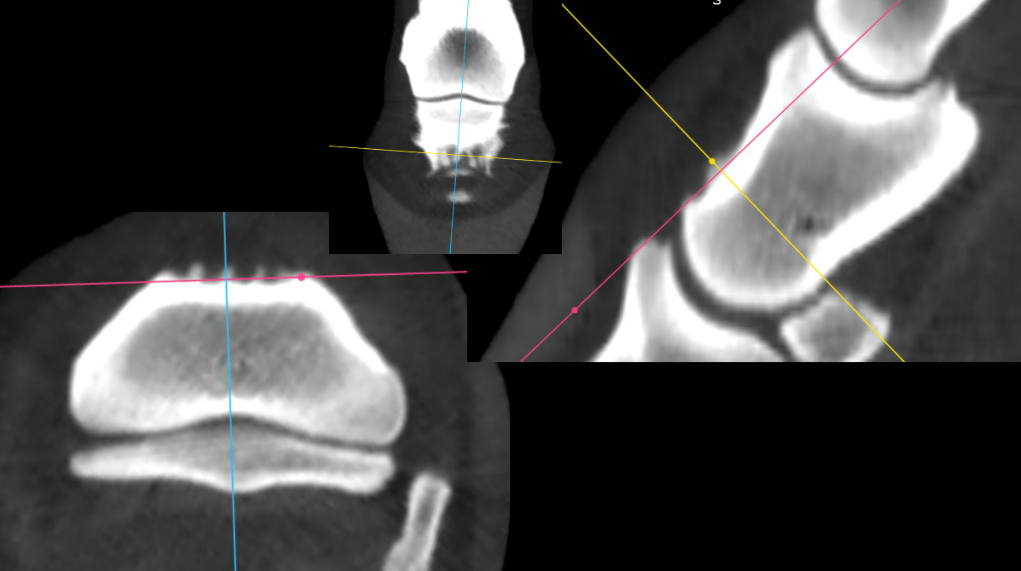

CT revealed an abnormality in the RF fetlock that was not visible on prior radiographs. The RF fetlock joint was injected with triamcinolone and hyaluronic acid (HA). If further treatment is required, biologics or polyacrylamide gels are recommended over corticosteroids. In cases where these treatments do not restore function, placing a screw distal to the subchondral defect may be considered.

Right Front shown above

• Radiographs initially suggested pathology in the coffin and pastern joints, which was confirmed by CT.

• However, radiographs did not reveal any abnormalities in the fetlock, whereas CT clearly identified the lesion.

• Adjusting image brightness and contrast further highlighted the lesion.